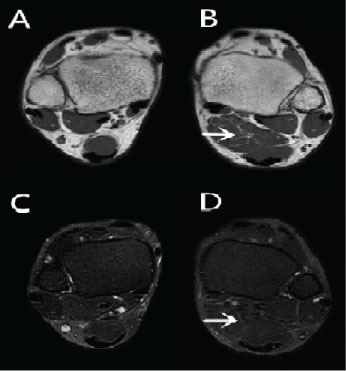

The MRI examination was performed using a 1.5-T MRI unit Signa Advantage Horizon; GE Medical Systems, Milwaukee, WI, USA. The T1 weighted coronal sequences showed the mass originating from the ventral portion of the normal soleus muscle and inserting to the medial surface of the calcaneus independently of Achilles tendon (Figure 1). Compared with the normal side, the affected side showed a homogeneous soft tissue mass located posteromedial to the flexor hallucis longus tendon and anteromedial to the Achilles tendon in all sequences (Figure 2, Figure 3 and Figure 4). It showed iso intense signal on all sequences (Figure 2, Figure 3 and Figure 4). And the pre-Achilles' fat pad was compressed by this muscle mass. The T1-weighted sequences showed a thin rim of adipose tissue within the fascial plane around the mass (Figure 1).

Figure 2: (B) Spin echo T1 weighted and (D) fast spin echo T2 weighted fat-suppressed axial images sequences shows that the accessory soleus muscle (arrow) had the same signal with adjacent muscles on all sequences. The A and C show the opposite side that is normal. View Figure 2